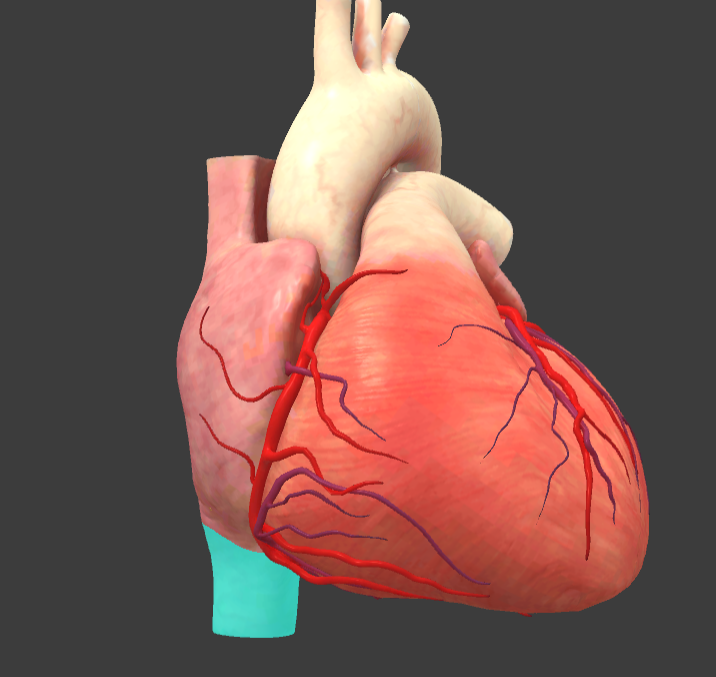

What is the name of the main vessels that supply the heart tissue with blood?

Coronary arteries

Right coronary a.